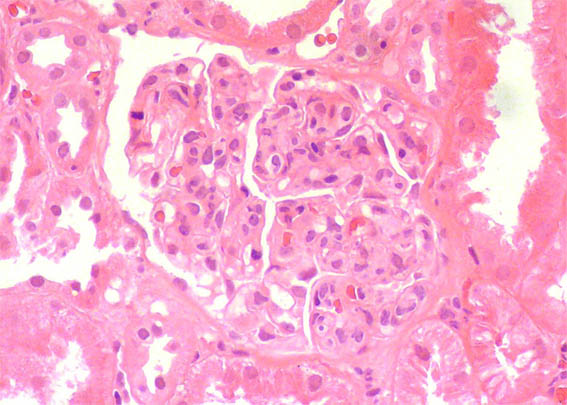

A renal biopsy was done, see the images.

Figure 3. H&E, X400.